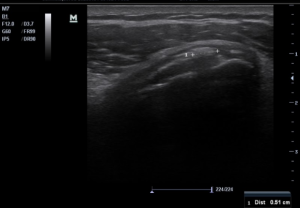

Ultrasound examination (Figures 1 and 2) conducted on the left shoulder showed 1) subscapularis calcific tendinopathy type 1 (4x5mm) and 2) infraspinatus calcific tendinopathy type 2 (14.4×15.6mm).

Figure 1. Indicates a subscapularis calcific tendinopathy